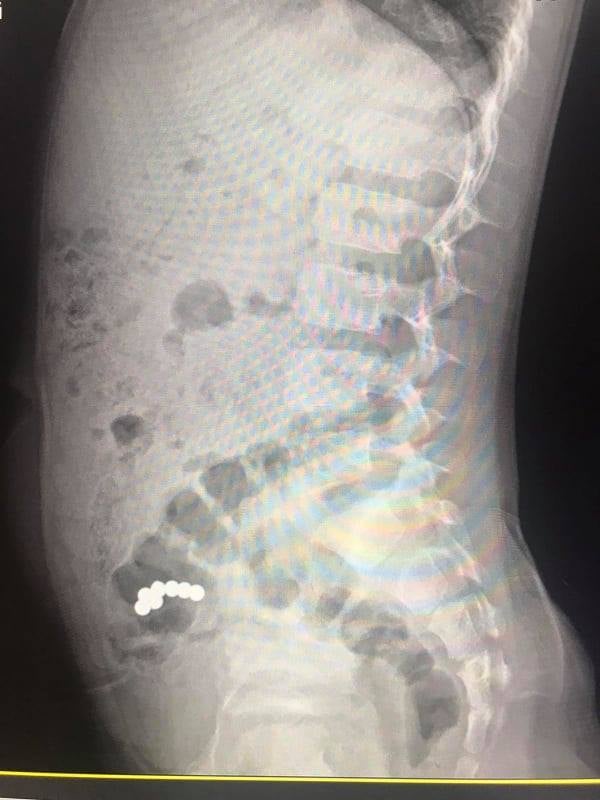

Під час рентгенологічного дослідження медики діагностували наявність магнітів в кишківнику, які не просуваються протягом 10 днів. Відсутність пасажу магнітів по кишківнику стало показанням до оперативного втручання. На операції виявили інтимне зрощення стінки тонкої кишки, де розташовані чотири магніти, зі стінкою сліпої кишки, де виявили три магніти.